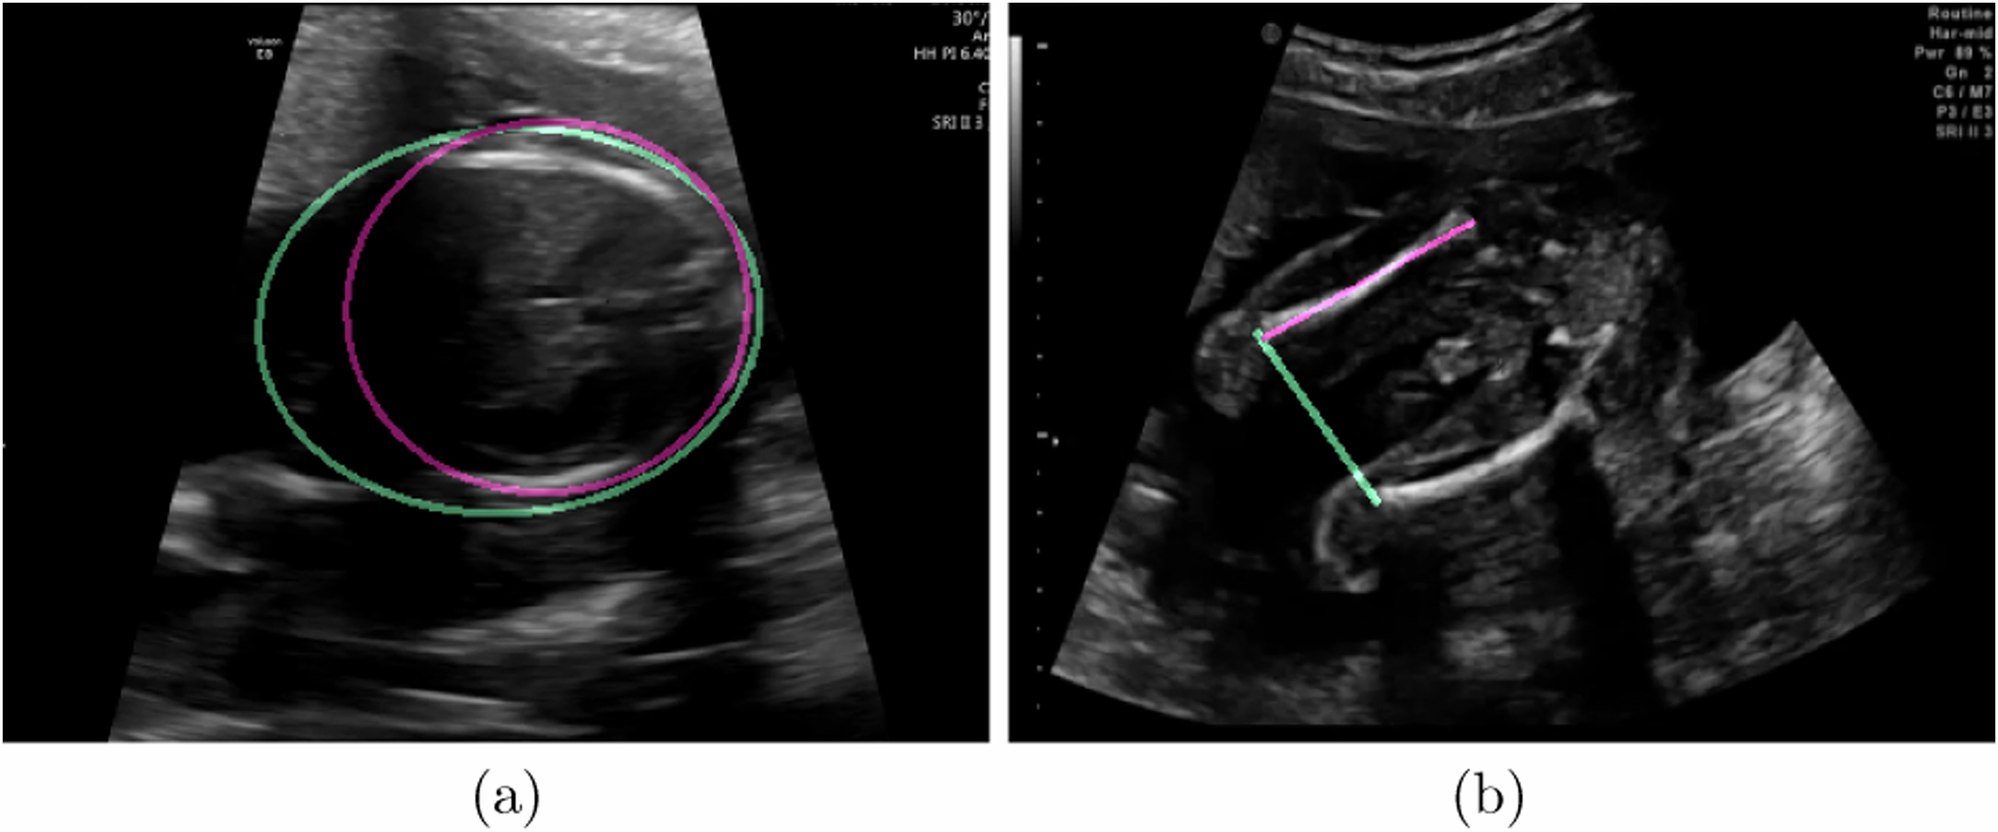

Fig. 5: Examples of failure cases in biometric estimation.

This figure shows two failure cases of biometric estimation in a the Head Circumference elliptical biometric and b the Femur Length linear biometric. The pink annotation shows the ground truth measurement made by a sonographer, while the green annotation is the automatic one made by our CNNs.